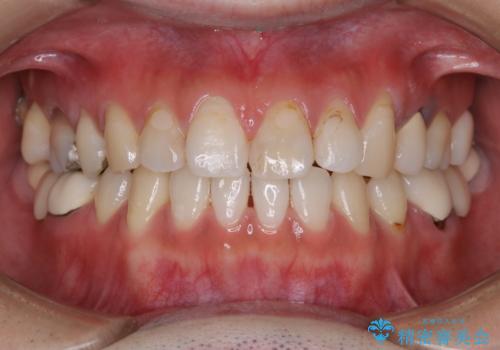

- 虫歯治療を始める前に、まずはしっかり汚れを取りたいとのことで来院されました。歯石やステインが分厚く付着していたため、PMTC60分コースを行いました。

歯の表面に、茶色く色が残っている所がありますが、これは詰め物の変色によるものです。以前に、CR(コンポジットレジン)による虫歯治療がされています。

CRは経年的劣化や、着色してしまうことがあります。PMTCでクリーニングを行うと、古いCRが目立つことがあるため、気になる際は詰め替えを行います。

茶色くなっている部分が、着色なのか、劣化なのか、虫歯によるものなのかは判別が難しいことがあります。そのため、定期的にPMTCを行うことで状態の確認が的確に行えます。